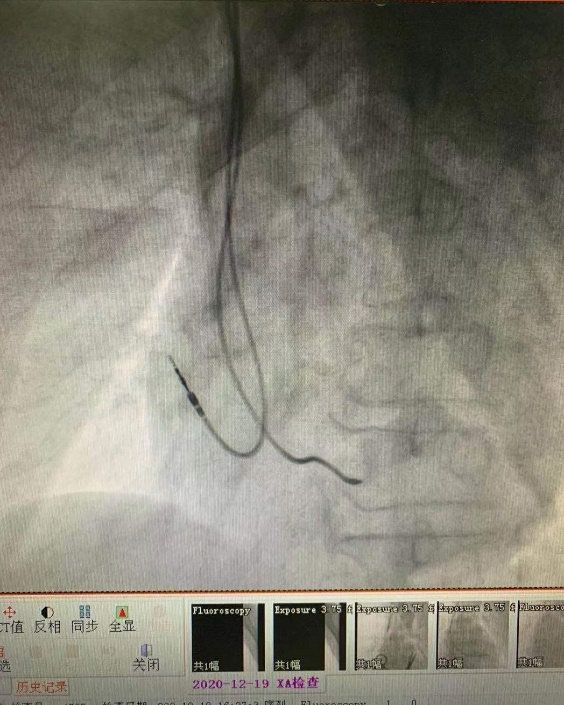

患者是一名76岁的男性,因晕厥入院,查动态心电图提示窦性停搏,最长RR间期2.84s,最慢心率只有33次。患者有两次晕厥病史,经诊断考虑为心室长时间停搏导致脑灌注不足引起的晕厥,若不及时安装永久起搏器,随时有心脏停博再次晕厥甚至猝死可能。科室团队进行了集体讨论,决定为患者实施双腔永久起搏器植入术。经家属及患者同意,心血管中心二区技术团队最终成功为患者植入双腔永久起搏器,术后患者头晕乏力等症状明显缓解,伤口愈合良好,顺利出院。

据心血管中心二区主任李玉梅介绍,病态窦房结综合征是由窦房结病变导致功能减退,产生多种心律失常的综合表现,主要临床症状是与心动过缓有关的心脑等脏器供血不足,如发作性头晕、黑朦、乏力等,严重者可发生晕厥。目前抗心律失常药物主要集中在快速性心律失常,心动过缓尚无特效的治疗药物,植入起搏器是确切有效的治疗手段,能有效改善患者症状,提高生活治疗,改善预后。起搏器主要通过一个约4cm的皮肤切口,埋在胸部皮下,通过电极导线连在心腔内,进而发放脉冲电流刺激心肌收缩。永久起搏器根据电极导线植入部位不同,又分为单腔起搏器及双腔起搏器,单腔起搏器为一个脉冲发生器及一根植入心房或心室电极,双腔起搏器为一个脉冲发生器、一根植入心房电极及一根植入心室电极,双腔起搏器的优势在于房室顺序起搏,符合生理性起搏模式,对病人心功能维护有较大的益处。